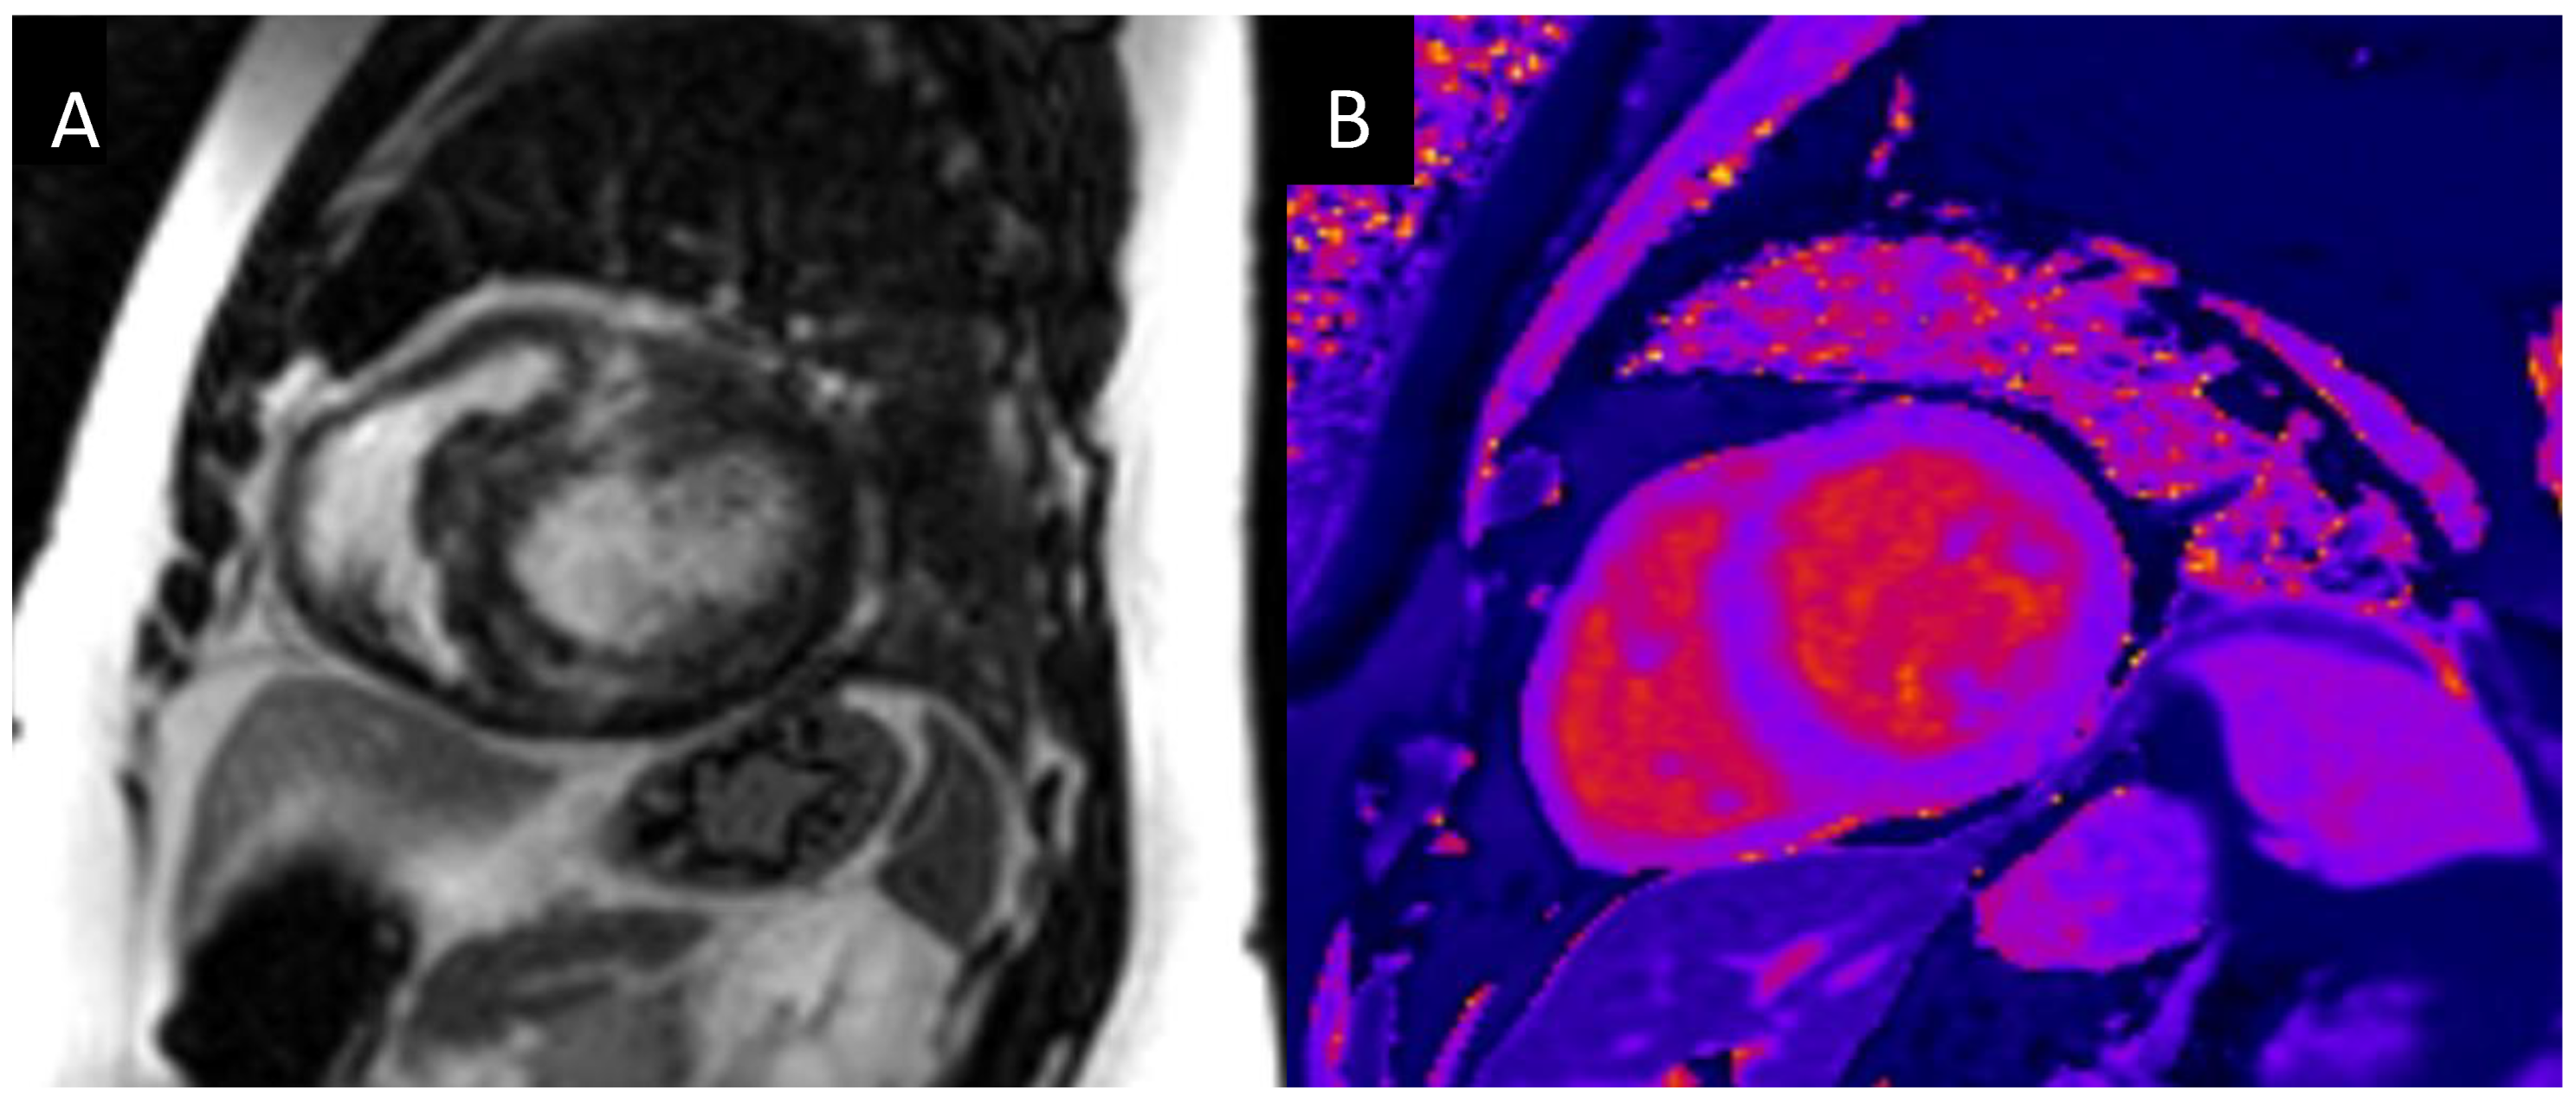

The EACVI Textbook of Cardiovascular Magnetic Resonance (The。4D-Flow Cardiovascular Magnetic Resonance Sequence for。Cardiovascular magnetic resonance physics for clinicians。在庫整理に伴う、出品です。表紙:きれい中身:きれい商品の状態は、中身の状態です梱包:緩衝剤リサイクル利用大型本の為、宅急便での発送となります。4D Flow cardiovascular magnetic resonance consensus。古いものですので時間経過によるシミ等についてはご理解下さい。J.M. Coetzee & Paul Auster 洋書セット。ストレンジャーシングス イレブン役 ミリー ボビー ブラウン 直筆サイン本。#洋書ぐぐ